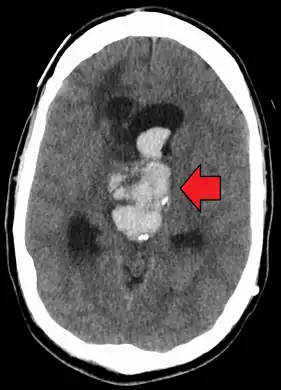

Evidence of intracranial hemorrhage on the left (brain cyst on right)

An acute bleed into a long-standing cystic mass within the brain. Arrow points to bleeding and mass.